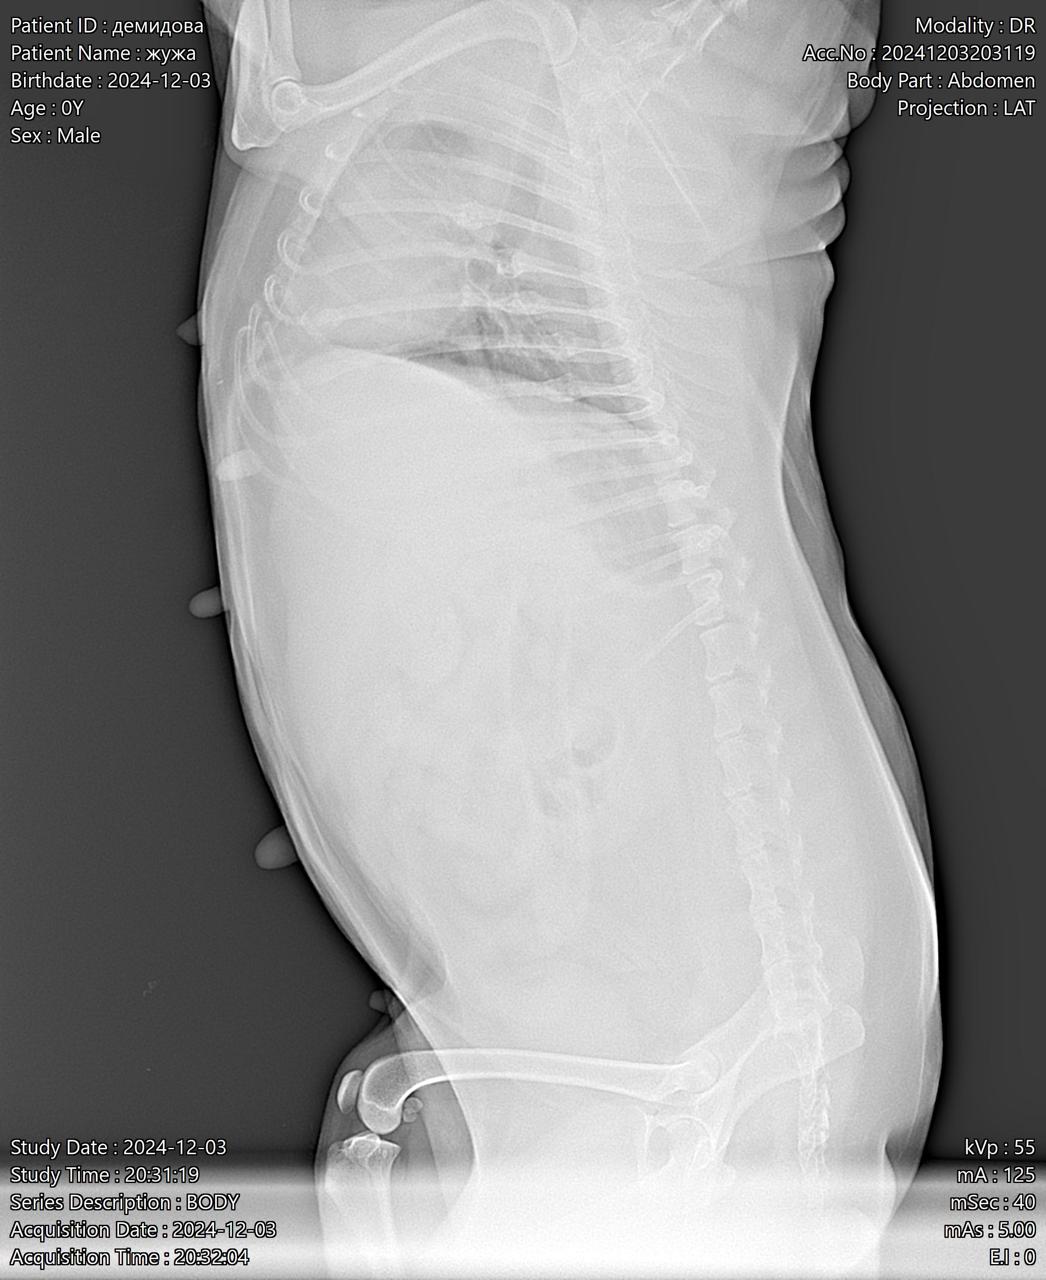

Визит к врачу с поносом